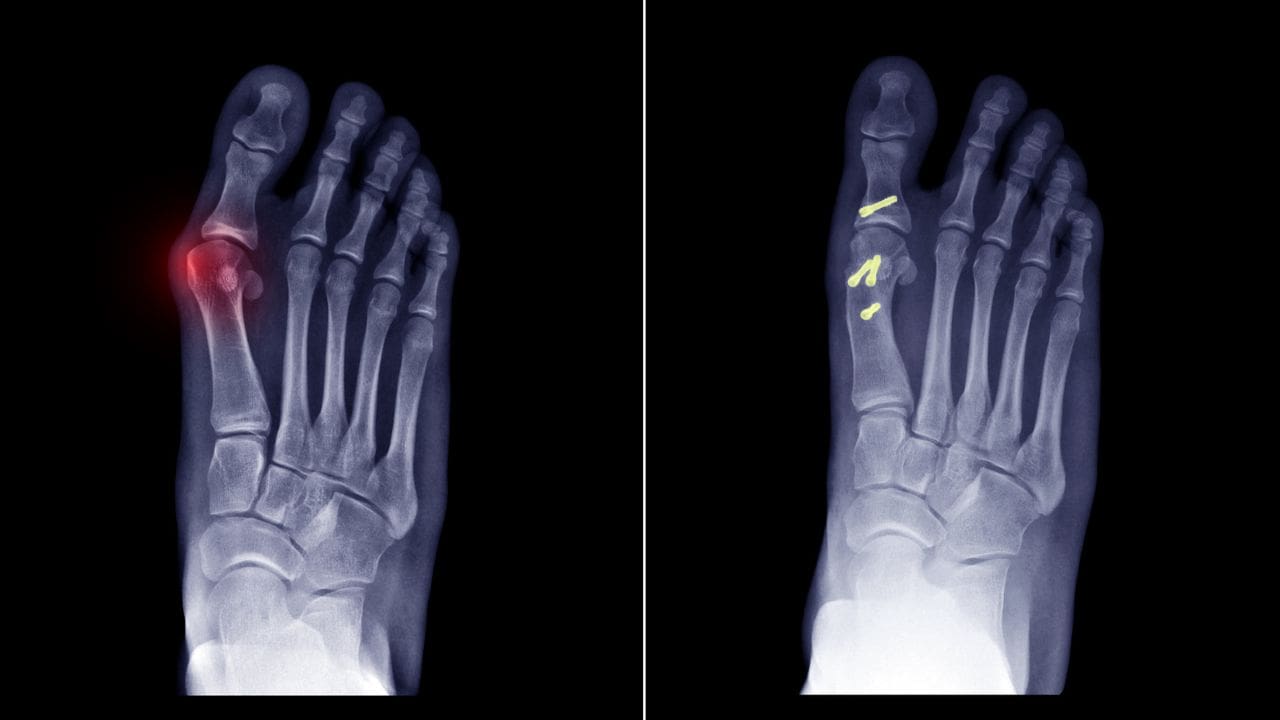

جراحی پا و مچ پا

در مواردی مانند آسیبهای ورزشی، شکستگی یا آرتروز شدید جراحی بر روی پا و مچ آن انجام میشود. در برخی اوقات گذاشتن پلاتین و پیچ کافی است، اما گاهی هم تعویض کامل مفصل ضرورت دارد.